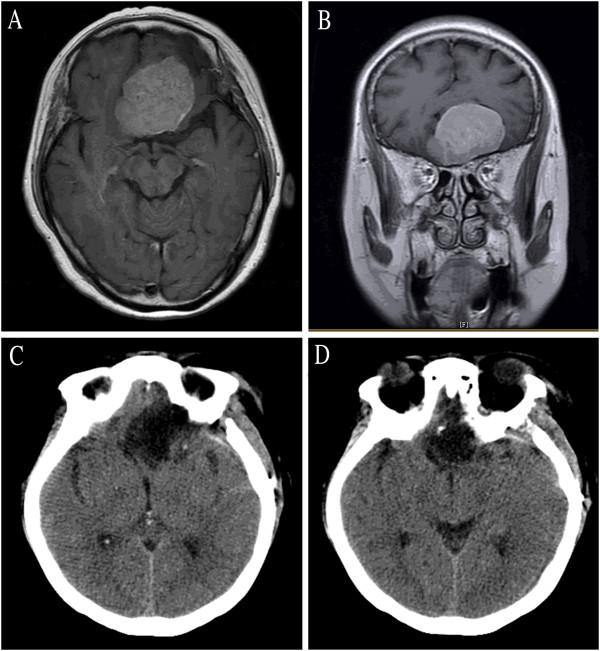

Between June 2011 and December 2011, 23 patients with neoplastic lesions underwent surgery by the corresponding author (ZW) via the LSO approach. The clinical presentations, neuroradiological findings, microsurgical techniques, and outcome at discharge of these patients were analyzed. In addition, the clinical series in the available literature written in English were also extensively reviewed. Eleven (48%) patients were treated for pituitary adenoma; six (26%) patients for tuberculum sellae meningioma; and six (26%) patients for craniopharyngioma.

Seemingly complete tumor removal was achieved in 21 patients (91%); surgical mortality was one patient (4.3%). Postoperatively, no patient had developed cerebrospinal fluid leakage or new visual deficits. One (4%) patient had intracranial infection, and one (4%) had a postoperative hematoma. The median Karnofsky score at discharge was 87.4 (range, 0 to 100). The Glasgow outcome scale at discharge was 4.6 (range, 1 to 5). Of all, 21 (91.3%) patients achieved favorable outcomes.